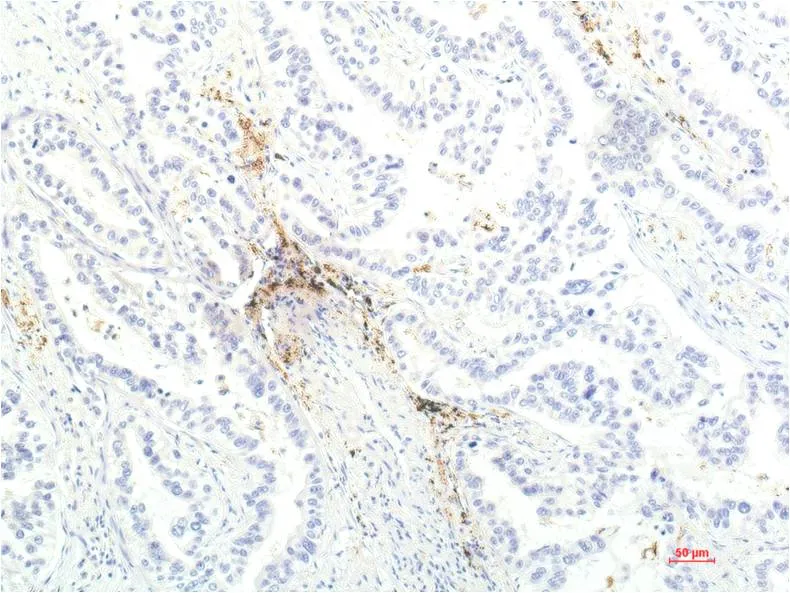

IL-8 (3A4) Mouse Monoclonal Antibody

Cat: AMM00739

Application:IHC-P

Reactivity:Human,Rat,Mouse

Conjugate:Unconjugated

Gene Name:CXCL8